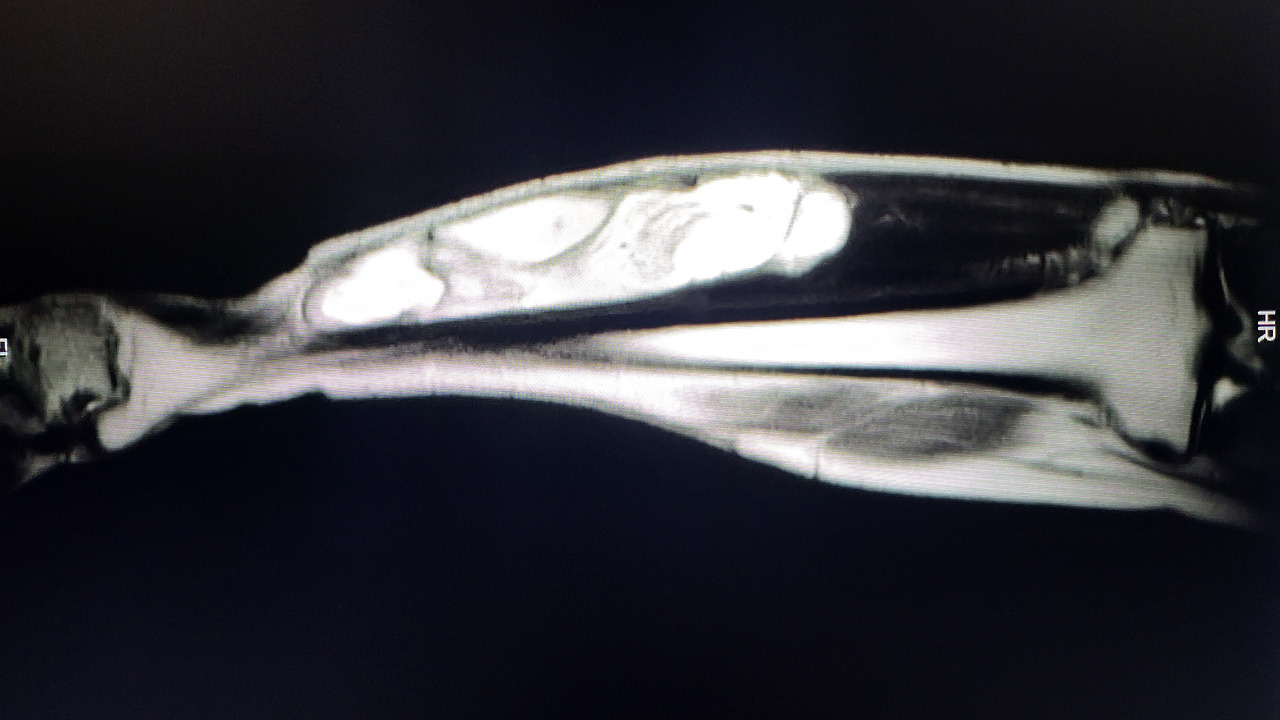

휴가 둘째 주, 동네에 MRI 촬영 가능한 2차 병원에서 MRI 촬영을 했을때 문제의 심각성을 알게 되었다. 그때 당시 의사는 종양사이즈가 20x4x4cm 정도 되고, 발목으로 전의되는 모습이 보이고 (나중에 이것은 저해상도 MRI로 인한 오판으로 결론남), 병명은 Mucinous Tumor로 추정된다고 알려주었다. 한국말로 정확한 병명조차 말해주지 못했던 의사 덕분에 병에 대해 많이 겁을 먹었다. 어쨋든 그 의사는 상급병원으로 가라고 했다.

오른쪽 앞 종아리에 생긴 길고 굵은 종양